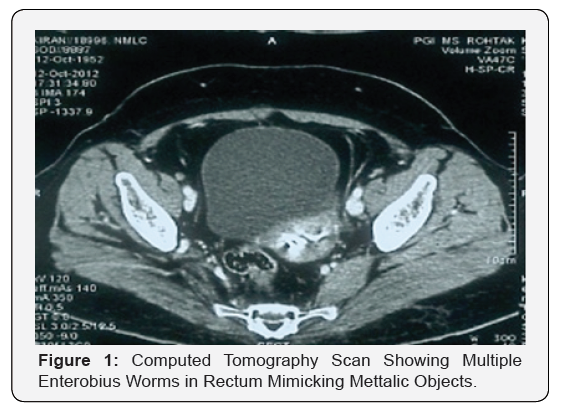

A 35-year-old woman presented to gynaecology department with the complaint of vaginal and perianal itching, pain abdomen, fever and generalized weakness for last one month. She was initially managed at some private hospital where Contrast Computed Tomography abdomen and pelvis was done due to refractory pain abdomen which revealed multiple metallic like foreign objects in anal canal and rectum. There she was suspected to be suffering from psychiatric disorder and thus was being evaluated for habit of putting some foreign objects in her anal canal and vagina. At this juncture, patient was admitted for proper evaluation and at time of admission she was toxic as evidenced by fever, leucocytosis and was anemiac. She was initially treated with intravenous fluids, antibiotics, two units of whole blood and after stabilization was subjected to colonoscopy which revealed multiple worms in anal Canal and rectum, few of which were retrieved for examination and were confirmed to be enterobius vermicularis i.e. pinworm. The patient was dewormed and within three days responded to treatment and was discharged under hemodynamically stable condition (Figure 1 & 2).